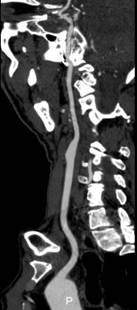

为满足广大瑞安市民更高更精准的诊疗需求,我院于今年投入巨资引进世界首款人工智能CT—Apex CT并开始临床运行。这款256排512层CT设备搭载世界首款深度学习图像重建(DLIR)引擎、高能量子球管和160mm超宽体探测器,采用kV/mA同步双瞬切技术,可实现无需屏气瞬时完成冠脉CTA成像、脑卒中成像一站式完成等功能,提高图像质量的同时降低辐射剂量。

Apex CT通过DLIR技术,突破以往CT需要多次打药、多次扫描的弊端,实现一次对比剂注射下得到CTA、CTV、灌注等临床所需图像,极大缩短抢救患者检查时间。